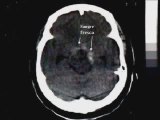

El Hospital Clínic de Barcelona conmemora este año la creación, hace 20 años, del Programa de Neurocirugía Funcional, el primero de estas características en implantarse en un hospital público en España. El Dr. Jordi Rumià, Coordinador del Programa, junto con los Coordinadores de las Unidades de Epilepsia y de Trastornos del Movimiento del hospital, pusieron en marcha este programa, gracias al que se han intervenido a cerca de 1.000 pacientes. La neurocirugía funcional es la rama de la neurocirugía que busca corregir aquello que funciona de forma anómala en el cerebro. Engloba, entre otras, la cirugía de la Epilepsia y la de los Trastornos del Movimiento y se aplica en aquellos casos en los que los pacientes no responden al tratamiento. En estos casos, las personas son muy dependientes y no tienen demasiadas opciones. Si se refieren a este tipo de unidades, son evaluadas por equipos multidisciplinares para ver si es adecuado o no llevar a cabo la intervención. “Es crucial detectar lo antes posible las resistencias a los fármacos, ya que si el paciente se puede operar, la recuperación es mejor y con menos secuelas“, señala el Dr. Jordi Rumià, coordinador del programa de Neurocirugía Funcional del Clínic y Sant Joan de Déu.